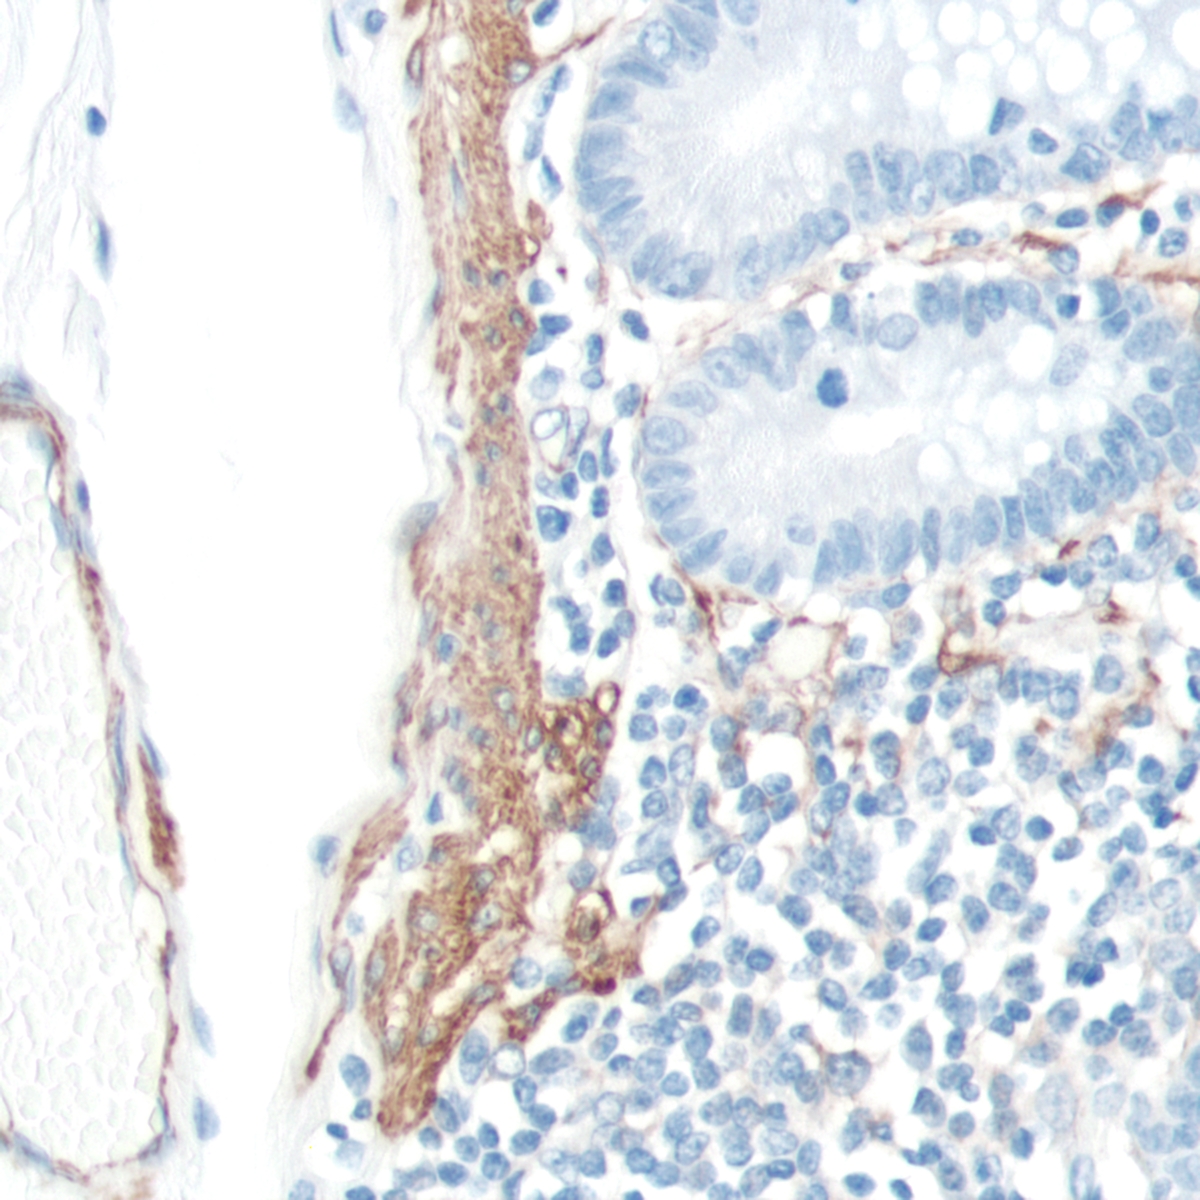

Actin-Smooth Muscle (SMA)

Smooth muscle actin-alpha (SMA) is a cytoskeleton protein in smooth muscle cells and their derived tumors such as leiomyoma and leiomyosarcoma. It is also expressed in myoepithelial cells of the breast and salivary gland, but not in fibroblasts, striated muscle, and myocardium.